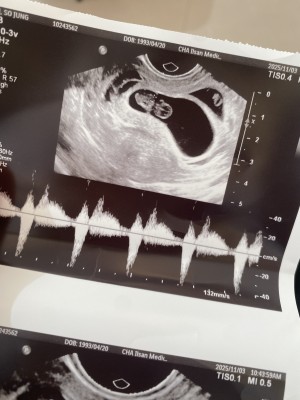

둘째아기천사가 엄마만나러 와줘서 너무고마워..

첫째는 두번유산에. 인공수정실패에.시험관으로 성공해서 정말 엄마가 많이많이 마중나가서 우리아기천사 만났는데 둘째아기천사는 생각지도못하게 자연적으로 딱 계획한 시기에 바로 엄마아빠에게 머나먼길을 직접 와줘서 너무너무고마워.. 엄마아빠오빠랑 얼른 곧 만나자. 너무너무사랑하고 감사합니다.